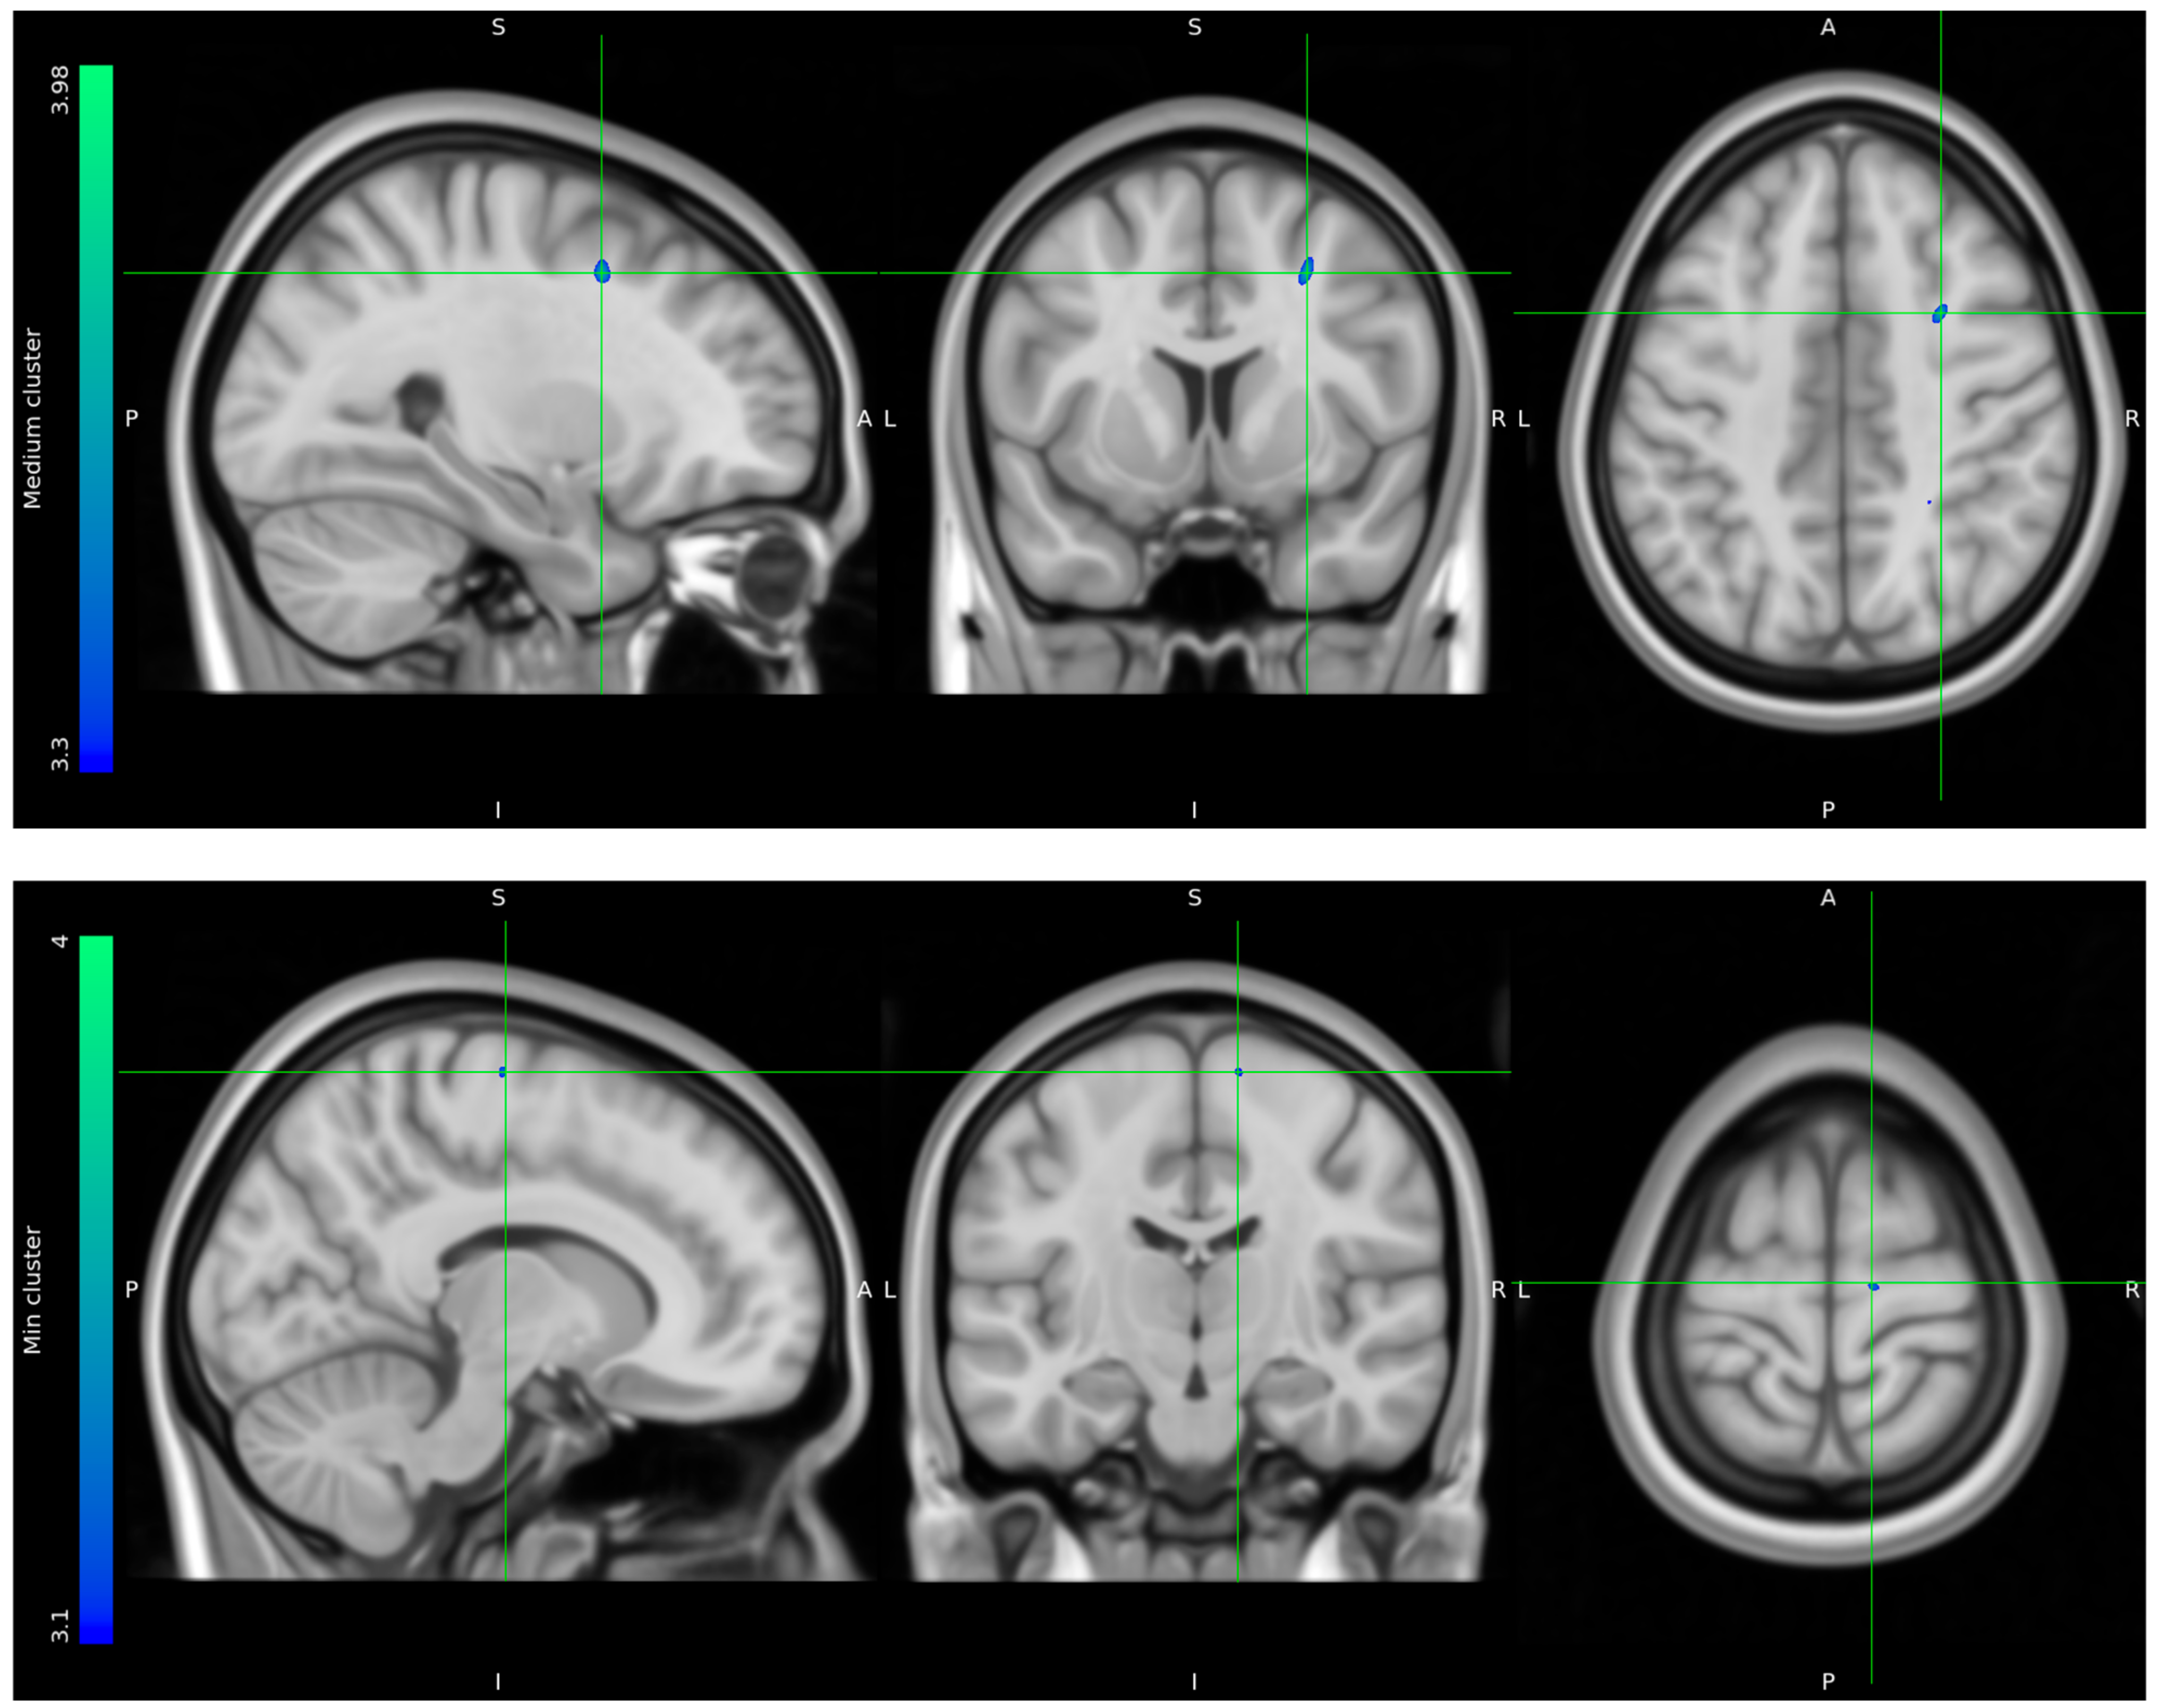

Due to data loss on the scanner, only 8 HCs and 10 stress patients were included in the brain imaging analysis. The one-tailed t-tests performed to evaluate voxels for which there was a directional-specific group difference (i.e., HC > stress or HC < stress) only showed effects in the HC > stress group. The one-tailed t-tests evaluating voxels for which there was a directional-specific group difference driven by a hypometabolic effect in stress patients compared to HCs identified three clusters with MNI coordinates [−30 24 24], left frontal lobe sub-gyral adjacent to middle frontal gyrus, [28 8 44] right frontal lobe middle frontal gyrus, and [12 −16 68] right frontal lobe precentral gyrus. Noticeably, the identified cluster appeared primarily to be located in the WM regions (Figure 5).

Figure 5.

FDG uptake illustrating a difference in glucose consumption between stress patients and healthy controls. Here, projected on MNI standard space template MNI152 0.5 with intensity threshold defined in color bar on the left. A: anterior, P: posterior, S: superior, I: inferior, L: left, R: right.

The results of the adapted version of the SCAN interview showed a clinical direction of stress patients experiencing physiological dysfunction as well as mental challenges in higher brain functions related to executive functions and emotion and mood regulation. Our FDG-PET imaging group analysis identified three clusters of voxel-wise differences in cerebral glucose metabolism between stress patients and HCs, where the stress patients had hypometabolic effects in areas primarily located in the white matter of the prefrontal cortex. The extracted suprathreshold cluster mean FDG uptake values for each participant expresses a consistent difference in the distribution between stress patients and HCs.